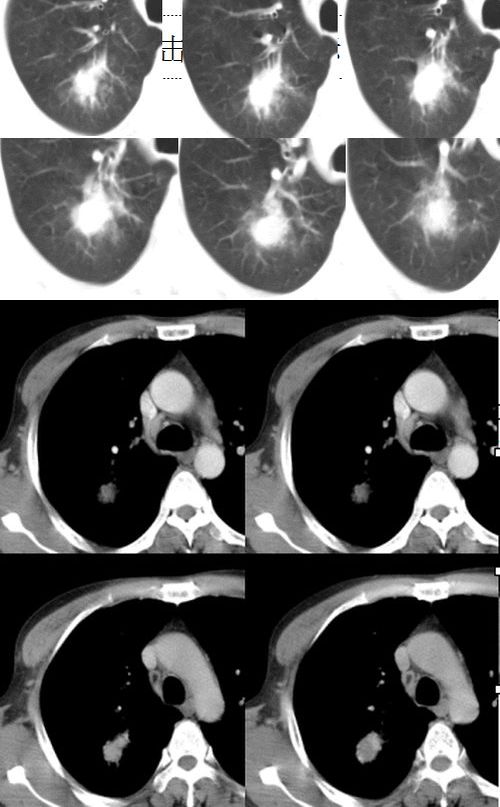

(1)发生部位:炎性假瘤可发生在两肺的任何部位,但多位于肺的表浅部位,邻近胸膜处或者靠近叶间裂。可以跨叶生长,原因可能是跨叶浸润的炎症使得假瘤跨叶融合的结果。

(2)假瘤形态:炎性假瘤的形态不一,可呈圆形.椭圆形或类圆形,也可呈驼峰状或不规则图形。

(3)假瘤大小:多数假瘤的直径在2-4cm,也可大于5cm,少数甚至大于10cm.

(4)假瘤密度:炎性假瘤一般为中等密度,密度均匀。而脓性炎症形成的假瘤则有时可见小空洞。空洞可以单发也可多发。少数瘤体切开时可见脓性物。

(5)假瘤边缘:

①有假无假性包膜者边缘清楚。有的由于肿块不规则可表现分叶状。

② 无假性包膜者,假瘤周围有纤维化和多种细胞成分侵润,表现为片状、边缘模糊的团块状影。或有轻度的渗出性病变,边缘模糊,以组织细胞围增生型多见。有的假瘤周围还可以出现类似周围型肺癌的放射冠状表现。

(6)邻近改变:位于肺周边部的假瘤,其邻近胸膜可见局限性粘连增厚。位于近肺门区的假瘤,偶可阻塞支气管,形成肺叶不张而将假瘤包裹,甚似中央性肺癌,但不出现肺门或纵膈淋巴结肿大。

(9)增强检查大多数肿块可见较显著的均匀强化,少数仅见肿块周围部强化甚或肿块不强化,这与肿块的组织结构成分,特别是血管成分有关。少数病人可见同侧肺门及纵隔淋巴结肿大,其直径常小于1.5cm.